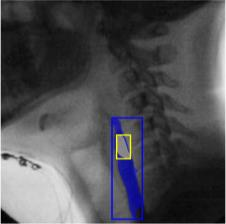

The videofluoroscopic swallowing study (VFSS) is a gold-standard imaging technique for assessing swallowing, but analysis and rating of VFSS recordings is time consuming and requires specialized training and expertise. Researchers have recently demonstrated that it is possible to automatically detect the pharyngeal phase of swallowing and to localize the bolus in VFSS recordings via computer vision, fostering the development of novel techniques for automatic VFSS analysis. However, training of algorithms to perform these tasks requires large amounts of annotated data that are seldom available. We demonstrate that the challenges of pharyngeal phase detection and bolus localization can be solved together using a single approach. We propose a deep-learning framework that jointly tackles pharyngeal phase detection and bolus localization in a weakly-supervised manner, requiring only the initial and final frames of the pharyngeal phase as ground truth annotations for the training. Our approach stems from the observation that bolus presence in the pharynx is the most prominent visual feature upon which to infer whether individual VFSS frames belong to the pharyngeal phase. We conducted extensive experiments with multiple convolutional neural networks (CNNs) on a dataset of 1245 bolus-level clips from 59 healthy subjects. We demonstrated that the pharyngeal phase can be detected with an F1-score higher than 0.9. Moreover, by processing the class activation maps of the CNNs, we were able to localize the bolus with promising results, obtaining correlations with ground truth trajectories higher than 0.9, without any manual annotations of bolus location used for training purposes. Once validated on a larger sample of participants with swallowing disorders, our framework will pave the way for the development of intelligent tools for VFSS analysis to support clinicians in swallowing assessment.